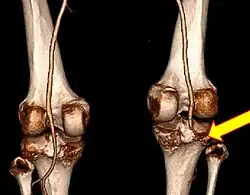

CT angiogram 3D reconstruction, posterior view showing a normal artery on the left, and occlusion to right popliteal artery as a result of a knee dislocation[11] -